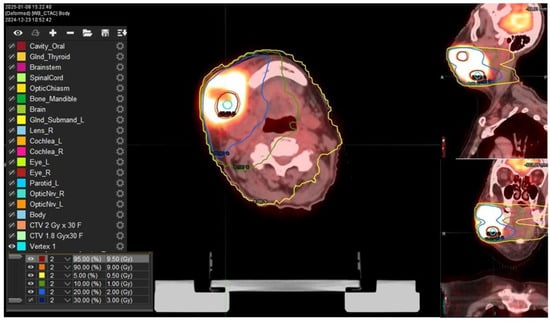

A bulky gross tumor volume (B-GTV) was delineated, encompassing both the primary tumor mass and the gross lymphadenopathies identified on imaging studies. We chose a “metabolism-guided” lattice radiation treatment planning that we have previously described [], delivering a spatially fractionated high radiation dose in two spherical deposits (vertices, Vs) within the bulky disease. Vs were allocated in a non-geometrical fashion between areas with different 18FDG/CT-PET metabolic activity levels (Figure 2). The dose delivered to the Vs was a single fraction of 10 Gy using a stereotactic volumetric modulated arc therapy (SVMAT) technique.

Figure 2. Isodose distribution of vertices utilized to create the dose inhomogeneity within the bulky disease (prescription dose 10 Gy in 1 fraction). Two vertices were applied at the interface between high-SUV and low-SUV areas. SFRT plan simulation was performed on PET-CT images coregistered with plan CT where there is a vertex (light blue), high isodose lines, the 95% (red line) and 90% (orange) of the prescription dose; and the low isodose line, delineating 5% (yellow line) of the prescription dose (0.5 Gy), 10% (green line) (1Gy), 20% (light blue line) (2 Gy), and 30% (dark blue line) 3 Gy.